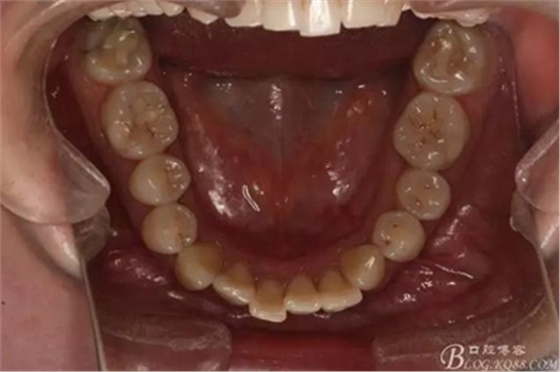

該病例主要為17、27頰側(cè)位同時伴有伸長,當(dāng)然種植支抗可以解決,但還有簡單實(shí)用的辦法嗎?如圖,在橫腭桿遠(yuǎn)中延伸出牽引鉤,位置盡量遠(yuǎn)離合平面,7粘舌側(cè)扣,牽引力的方向?yàn)閴旱图吧嘞?,下圖為兩個月的效果,17已到位,27還未到位。